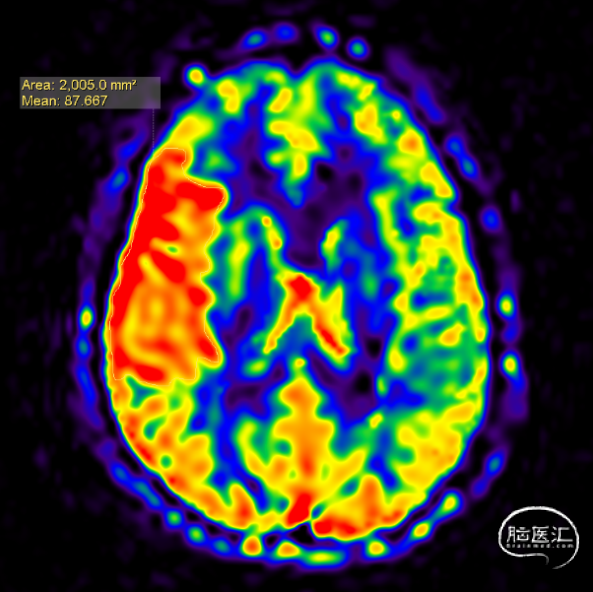

颅脑灌注成像提示高灌。